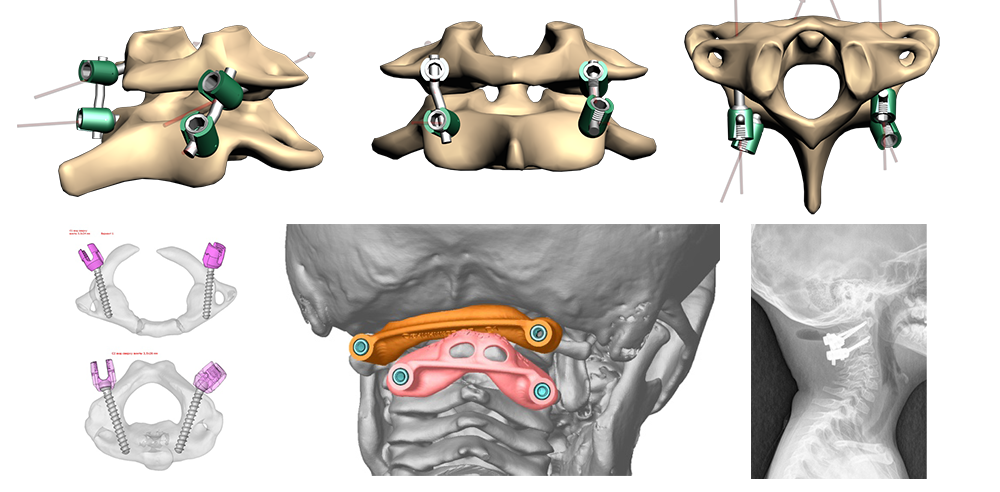

Важно сохранить подвижными максимальное количество позвоночно-двигательных сегментов. Во время подготовки к операции используются данные компьютерной томографии для расчетов размеров костных структур и безопасной траектории для проведения винтов. При необходимости создается объемная модель шейных позвонков и специальные направляющие на 3Д принтере.

На рис.: схема минимальной фиксации атланта и аксиса с помощью 2-х пар титановых винтов (техника по Goel-Harms), соединенных титановыми стержнями. Схема установленных на позвонки направителей для винтов, изготовленных на 3Д принтере. Рентгенограммы ребенка 5 лет после проведения данной операции.